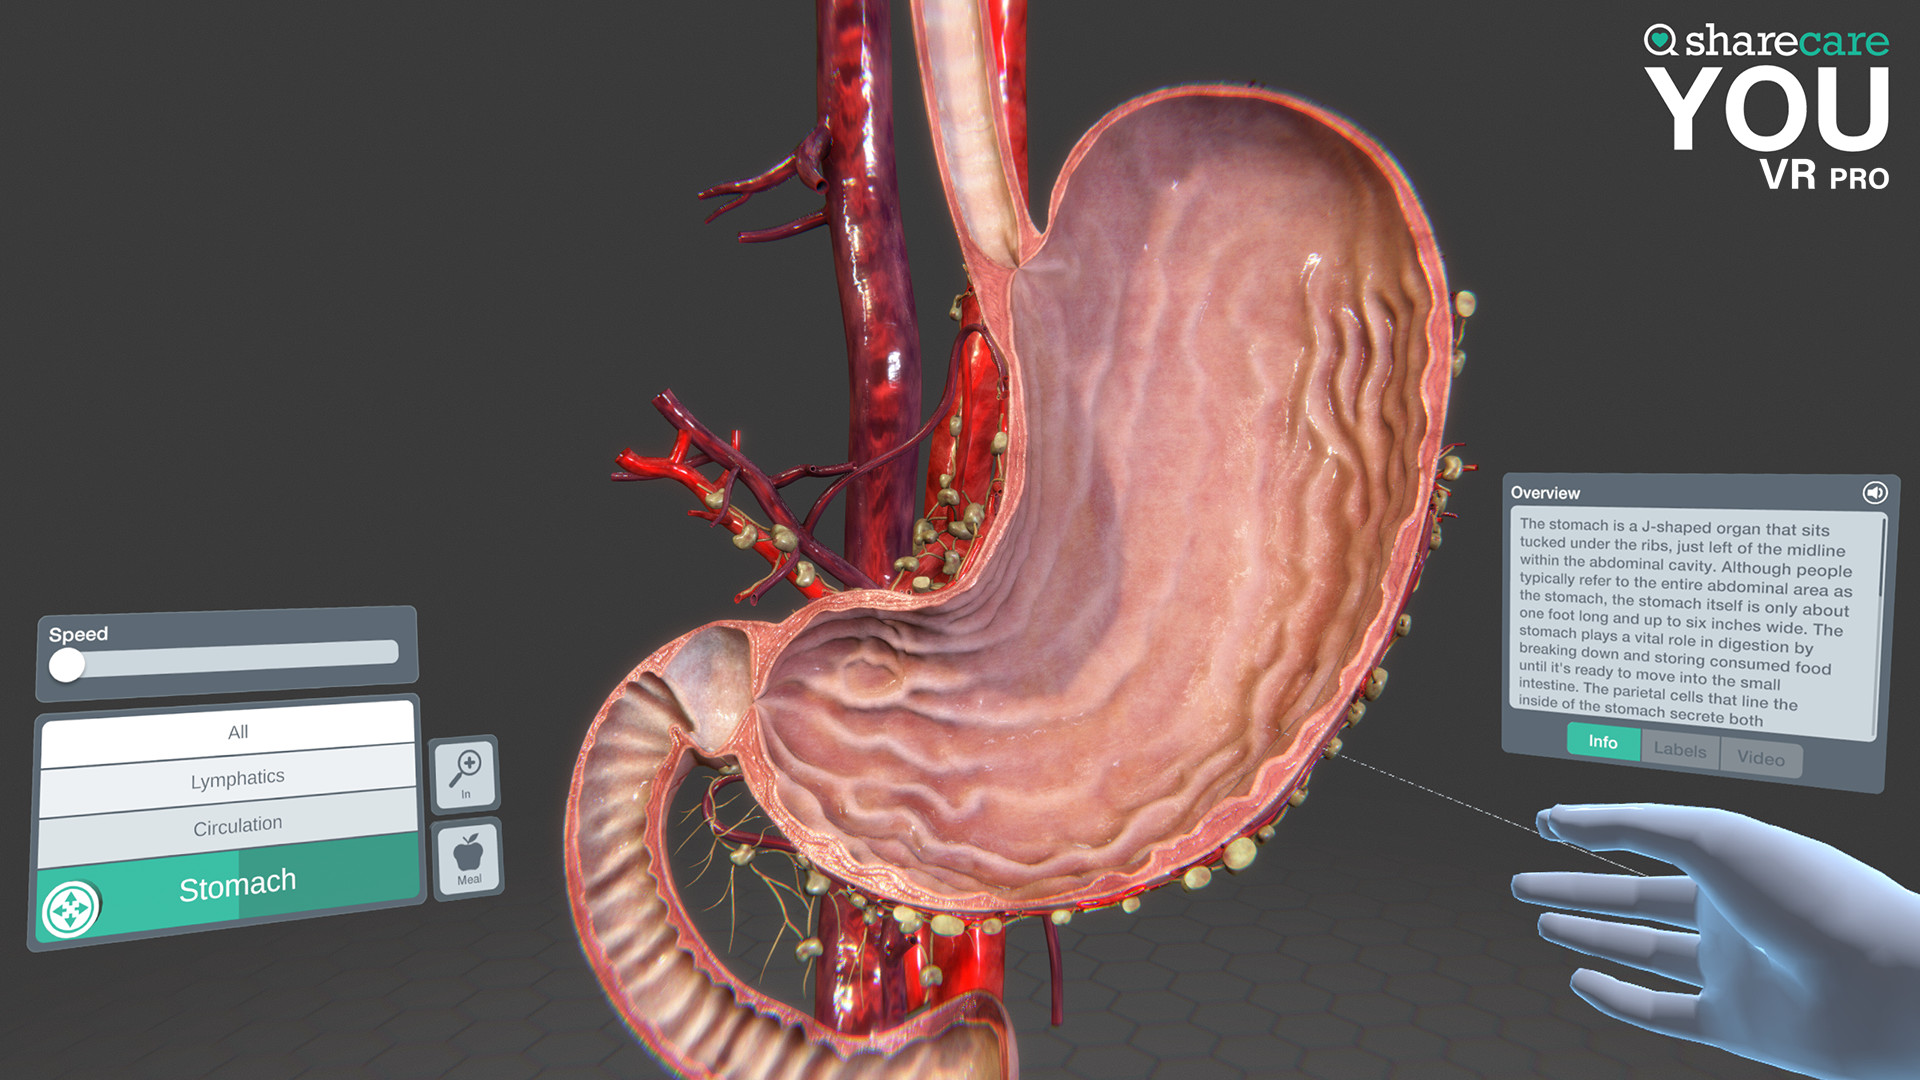

The winner of the 2019 Appy Best VR App is now available on Mac and PC, with more content, bolder graphics, and enhanced features! Sharecare YOU VR is a fully immersive, photorealistic simulation of the human body, enabling anyone to explore its astonishing details in full 360 degrees. Interested in learning about a specific organ? With the click of a button, travel inside, visualize its natural function, and dive deeper. Want to learn even more? Check out the many tags and labels along the way to gain even more information and insight. Easily customize YOU to better understand physiology and simulate disease. You can even personalize our avatars to be a virtual you – your health, your conditions. It really is all about YOU. With YOU VR PRO, users can create visually compelling, high-quality educational content. Build YOU lectures and presentations easily, with the help of video and voiceover recording, and the ability to draw and add your own text. You can also be the star within these videos using our web-cam feature.

- YOU content - an expanding library of over 40 different scenes to explore including anatomy, physiology, conditions, and treatments

- Informative labels and scene information

- Completely updated user interface with unique interactive controls

Looking to use the content for Business Purposes? Get the Sharecare YOU VR Pro version and have the ability to use all the amazing content for Business Purposes. Take advantage of breathtaking graphics and never seen before views of the human body. Your ability to better communicate human anatomy and physiology with your customers and/or students is at your fingertips!